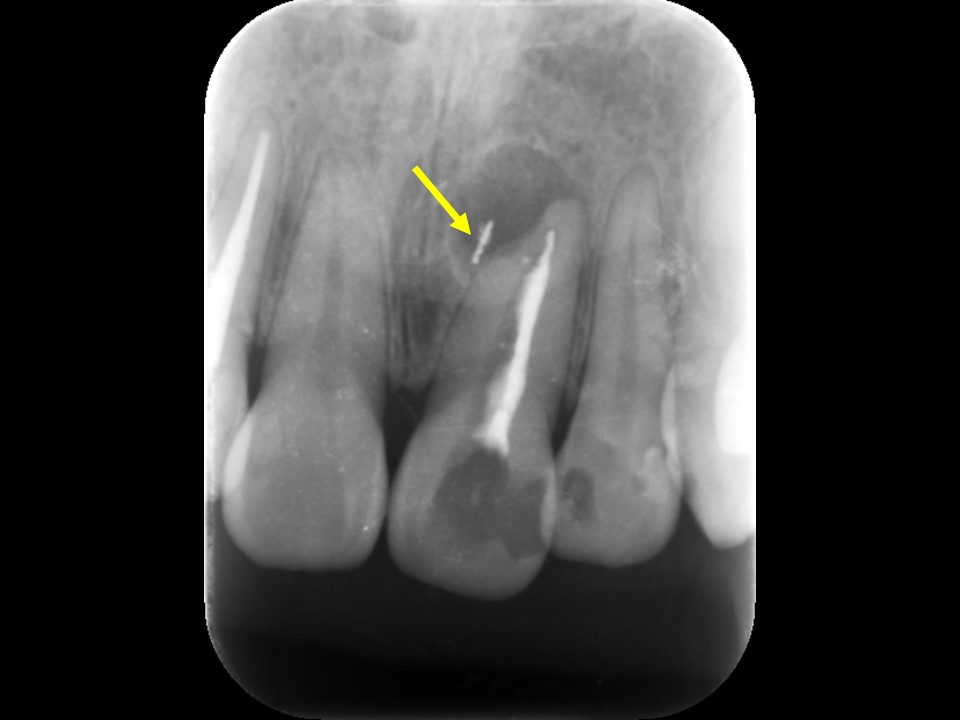

上顎前歯部は根管充填されているものの不十分で、歯根の先端には根尖病変と思われるX線透過像を認めます。以前の治療で根尖部はすでに壊れており、根尖外には破折したファイルが迷入しています(矢印)。外科的にファイルの撤去が必要なケースです。

術前レントゲンおよびCT画像です。上顎前歯に連結したセラミッククラウンが装着してありますが、根管充填は不十分です。

根尖部には根尖病変と思われる黒いX線透過像を認めます(矢印)。すでに一度歯根端切除が行われているため、隣在歯と比べて歯根が短くなっています。